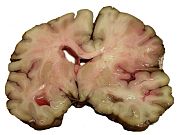

Intracerebral hemorrhage (ICH) is bleeding directly into the brain tissue, forming a gradually enlarging hematoma (pooling of blood). It generally occurs in small arteries or arterioles and is commonly due to hypertension, trauma, bleeding disorders, amyloid angiopathy, illicit drug use (e.g. amphetamines or cocaine), and vascular malformations. The hematoma enlarges until pressure from surrounding tissue limits its growth, or until it decompresses by emptying into the ventricular system, CSF or the pial surface. A third of intracerebral bleed is into the brain's ventricles. ICH has a mortality rate of 44 percent after 30 days, higher than ischemic stroke or even the very deadly subarachnoid hemorrhage.